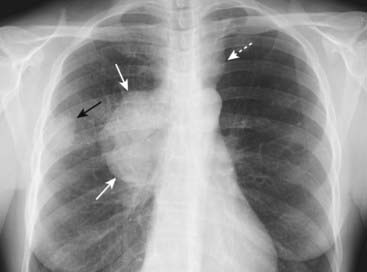

Figure 12-19 Bronchogenic carcinoma with lymphangitic spread of tumor.

In lymphangitic spread of carcinoma, a tumor grows in and obstructs lymphatics in the lung producing a pattern that is radiologically similar to pulmonary interstitial edema from heart failure. The findings may be unilateral, as in this case, which should alert you to the possibility of lymphangitic spread rather than congestive heart failure. There is extensive hilar and mediastinal adenopathy (solid black arrows) from a carcinoma of the lung. The interstitial markings are prominent in the right lung compared to the left, and there are thickened septal lines (Kerley B lines) present (solid white arrows) along with a right pleural effusion (dotted black arrow).

image In lymphangitic spread of carcinoma, a tumor grows in and obstructs lymphatics in the lung, producing a pattern that is radiologically similar to pulmonary interstitial edema from heart failure including Kerley B lines, thickening of the fissures, and pleural effusions.

imageThe findings may be unilateral or may involve only one lobe, which should alert you to suspect the possibility of lymphangitic spread rather than congestive heart failure, which is usually bilateral (Fig. 12-19).

image The most common primary malignancies to produce lymphangitic spread to the lung are those that arise around the thorax: breast, lung, and pancreatic carcinoma.